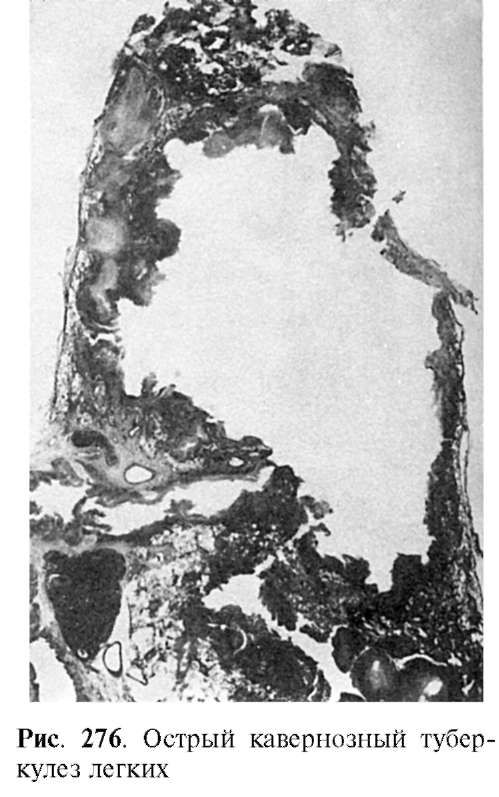

Понимание кавернозного туберкулеза почки